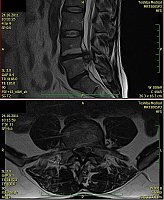

2. Muž, 41 let. Na MR objemná hernie L4/5 velikosti 11mm téměř vyplňující páteřní kanál, útlak nervových kořenů. Opakovaně doporučována operace, kterou pacient odmítl. Jako alternativu zvolil ozonoterapii s aplikací ozonu do disku L4/5 a periradikulárně. Byly aplikovány celkem 3 dávky ozonu. Viz obr.7a

Na kontrolním MR po 6 měsících je patrná výrazná redukce velikosti hernie, vymizely fragmenty, uvolnil se páteřní kanál a do značné míry i nervové kořeny. Subjektivně výrazná úleva téměř k normálu. Viz obr. 7b